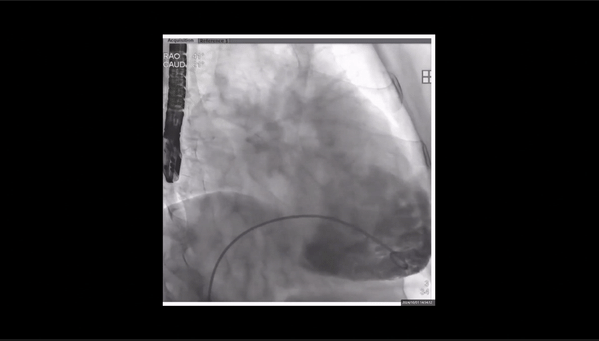

夾持件位置確認(rèn)

室間隔位置確認(rèn)